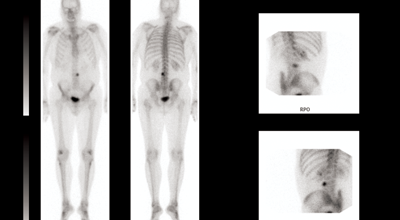

Of the nine patients who had metastasis from prostate cancer, four had a solitary bone metastasis and five had isolated lymph node disease, three within the pelvis and two para aortic nodes. The median age at treatment was 67, range 50-73. Median follow-up was 13.8 months, range 0.3-23.0 months with local control to date of 100%. Five (56%) patients have no evidence of disease. Four patients have developed other sites of disease but have continued to have local disease control in the irradiated metastasis. The time from treatment to the development of other sites of disease is 14.0 months median, range 6.6-20.2 months. Three patients have subsequently died from metastatic disease. There has been no grade three or four toxicity with the majority having no recorded side-effects. From our very limited series we concluded that despite relatively limited follow-up, our series confirms excellent local control with SBRT and that SBRT may alter the outcome for men with oligometastatic prostate cancer and delay initiation of androgen deprivation and systemic therapies, but that randomised control data is required to confirm the role of SBRT in prostate cancer.

I thought it would be helpful to illustrate a couple of our cases which indicate the effect of stereotactic radiotherapy and its possible future use in the overall management of metastatic prostate cancer.